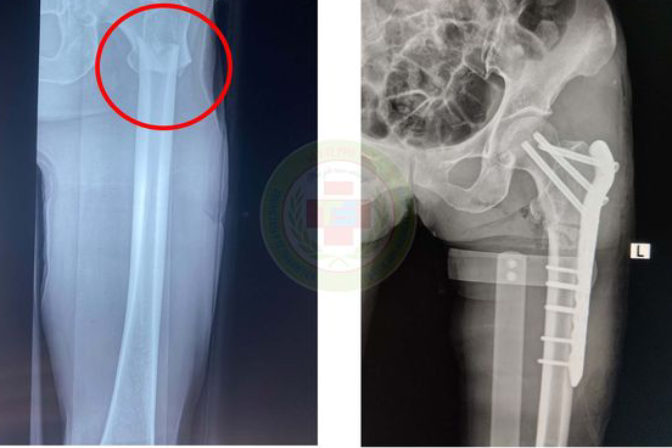

Ngay sau khi vào viện, các bác sĩ chẩn đoán sơ bộ gãy xương đùi bên trái. Lập tức, bệnh nhân đã được xử trí cấp cứu giảm đau, chống sốc kịp thời và được đưa đi làm các cận lâm sàng cần thiết. Kết quả chụp X-quang cho thấy hình ảnh gãy ngang đầu trên xương đùi bên trái, di lệch hoàn toàn. Sau phẫu thuật, người bệnh ổn định và sức khỏe đang hồi phục tốt.